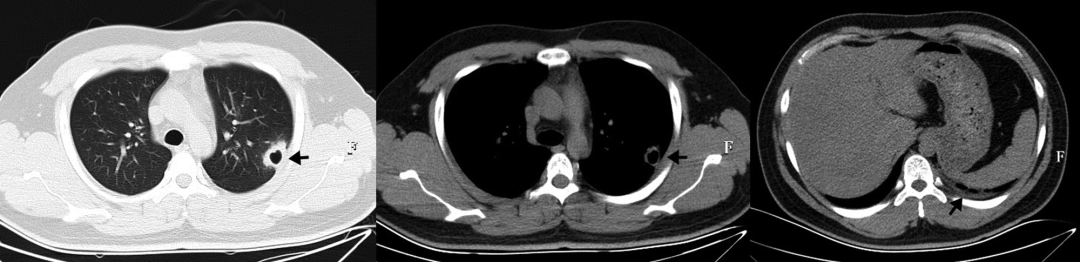

• 肺部CT显示多灶性双侧毛玻璃影(图3)

图3:入院时肺部CT显示多灶性双侧毛玻璃样阴影

• 治疗5天后(第6天),肺部CT显示病情比治疗前更严重(图4)。NGS的结果回报耶氏肺孢子菌特异性序列数为205658,覆盖度为1.70%,TW特异性序列数为 115,覆盖度为1.00%。qPCR显示TW的拷贝数为11717.3拷贝/ml

图4:肺部CT提示双肺发生多发感染,第6天存在散在弥漫性斑片状、磨玻璃样、高密度影